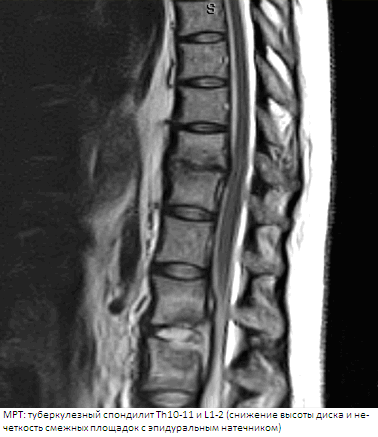

МРТ (магнитно-резонансная томография) обладает большим преимуществом при выявлении туберкулезного остита, позволяет прижизненно изучить динамику туберкулезного процесса, отражает протяженность паравертебральных абсцессов, дает возможность оценить состояние межпозвонкового диска, позвоночного канала, спинного мозга, его оболочек, компримирующего субстрата. Таким образом, показаниями к использованию МРТ являются: все случаи спинномозговых расстройств; необходимость уточнения протяженности компримированного участка спинного мозга; отсутствие изменений на рентгенограммах при наличии жалоб и клиники спинального дефицита; спондилит субокципитальной и шейно-грудной локализации; выявление абсцессов, их протяженности, связи с позвоночником и другими органами, в том числе при атипичном течении туберкулезного спондилита; сохраняющиеся неврологические нарушения после декомпрессивной операции. Использование МРТ не показано при наличии металлических конструкций в позвоночнике, искусственного водителя ритма сердца, металлических клемм на сосудах и др.

• Сагиттальные STIR и FSE T2 МР-И наиболее чувствительны в отношении диагностики отека костного мозга, поражения эпидурального пространства:

о МРТ считается наиболее информативной методикой, позволяющей оценить протяженность поражения и ответ на проводимую терапию